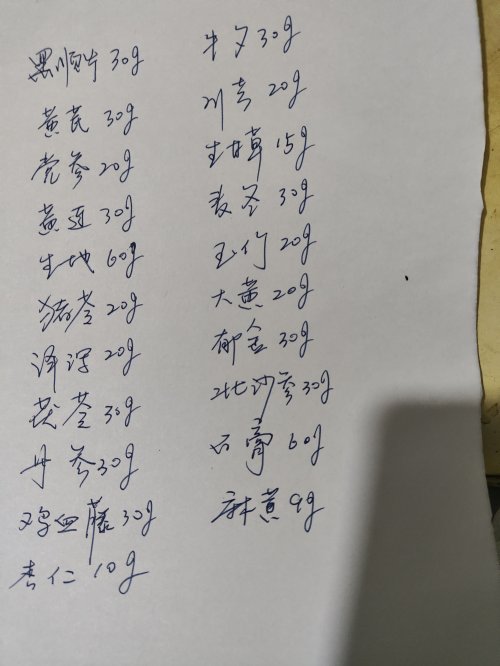

向各位医生求救,我母亲中风瘫痪,长期卧床,有心衰,还好遇到一名好心的中医,开了方子活到现在,可是这一次有严重的肺炎,我从网上找了新冠的方子——清肺排毒汤,医生说可以吃,吃了9天改善很大,可是还是有痰,舌苔发黄,医生说是热症,也有可能长期附子的关系,呼吸还是受肺部炎症影响。后来针对我妈的问题医生又开了一个方子,里面有麻杏石甘汤和五苓散,吃了几天肺炎没什么改善,这几天又点重了,经常冒虚汉,今天没办法只能找西医过来挂水,希望有改善。我想中西医结合起来,能好的快一些,请问清肺排毒汤继续吃,还是加减,或有其它方子推荐也可,请各位医者帮帮忙,感谢。

附上舌苔和药方。

附上舌苔和药方。